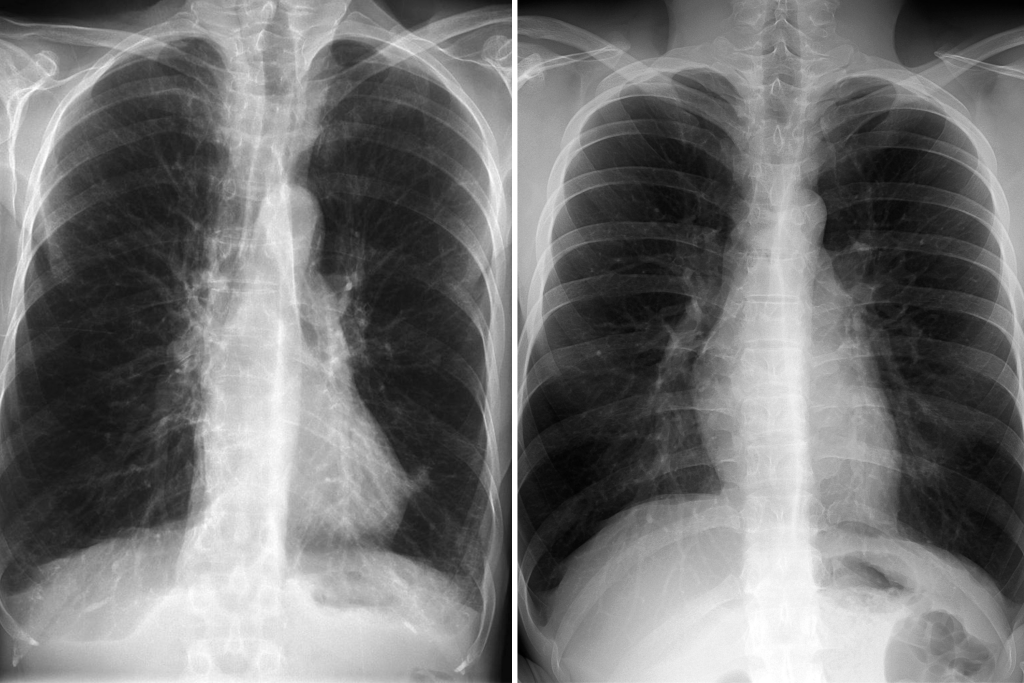

Smoking is the single biggest threat to lung health at any age, but it’s especially harmful for seniors. It accelerates lung tissue damage, increases the risk of chronic obstructive pulmonary disease (COPD)—a leading cause of disability in older adults—and raises the chance of lung cancer.

When to See a Doctor: Warning Signs

See your doctor immediately if you experience:

- Persistent cough (lasting more than 3 weeks)

- Shortness of breath during everyday activities

- Chest pain or tightness when breathing

- Wheezing or coughing up blood

- Unintended weight loss or fatigue